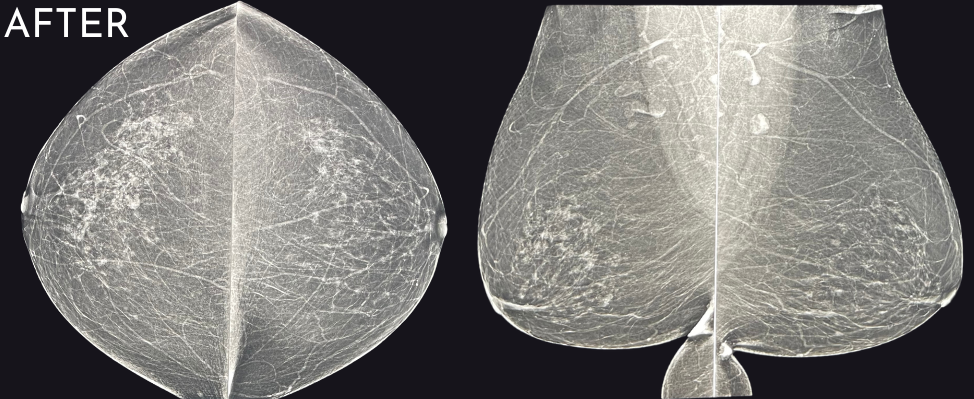

When comparing “before” and “after” images, the improvement can often be startling, even if the original images were really good! We have even identified cancers that were not visualized the year prior. Now that is amazing!